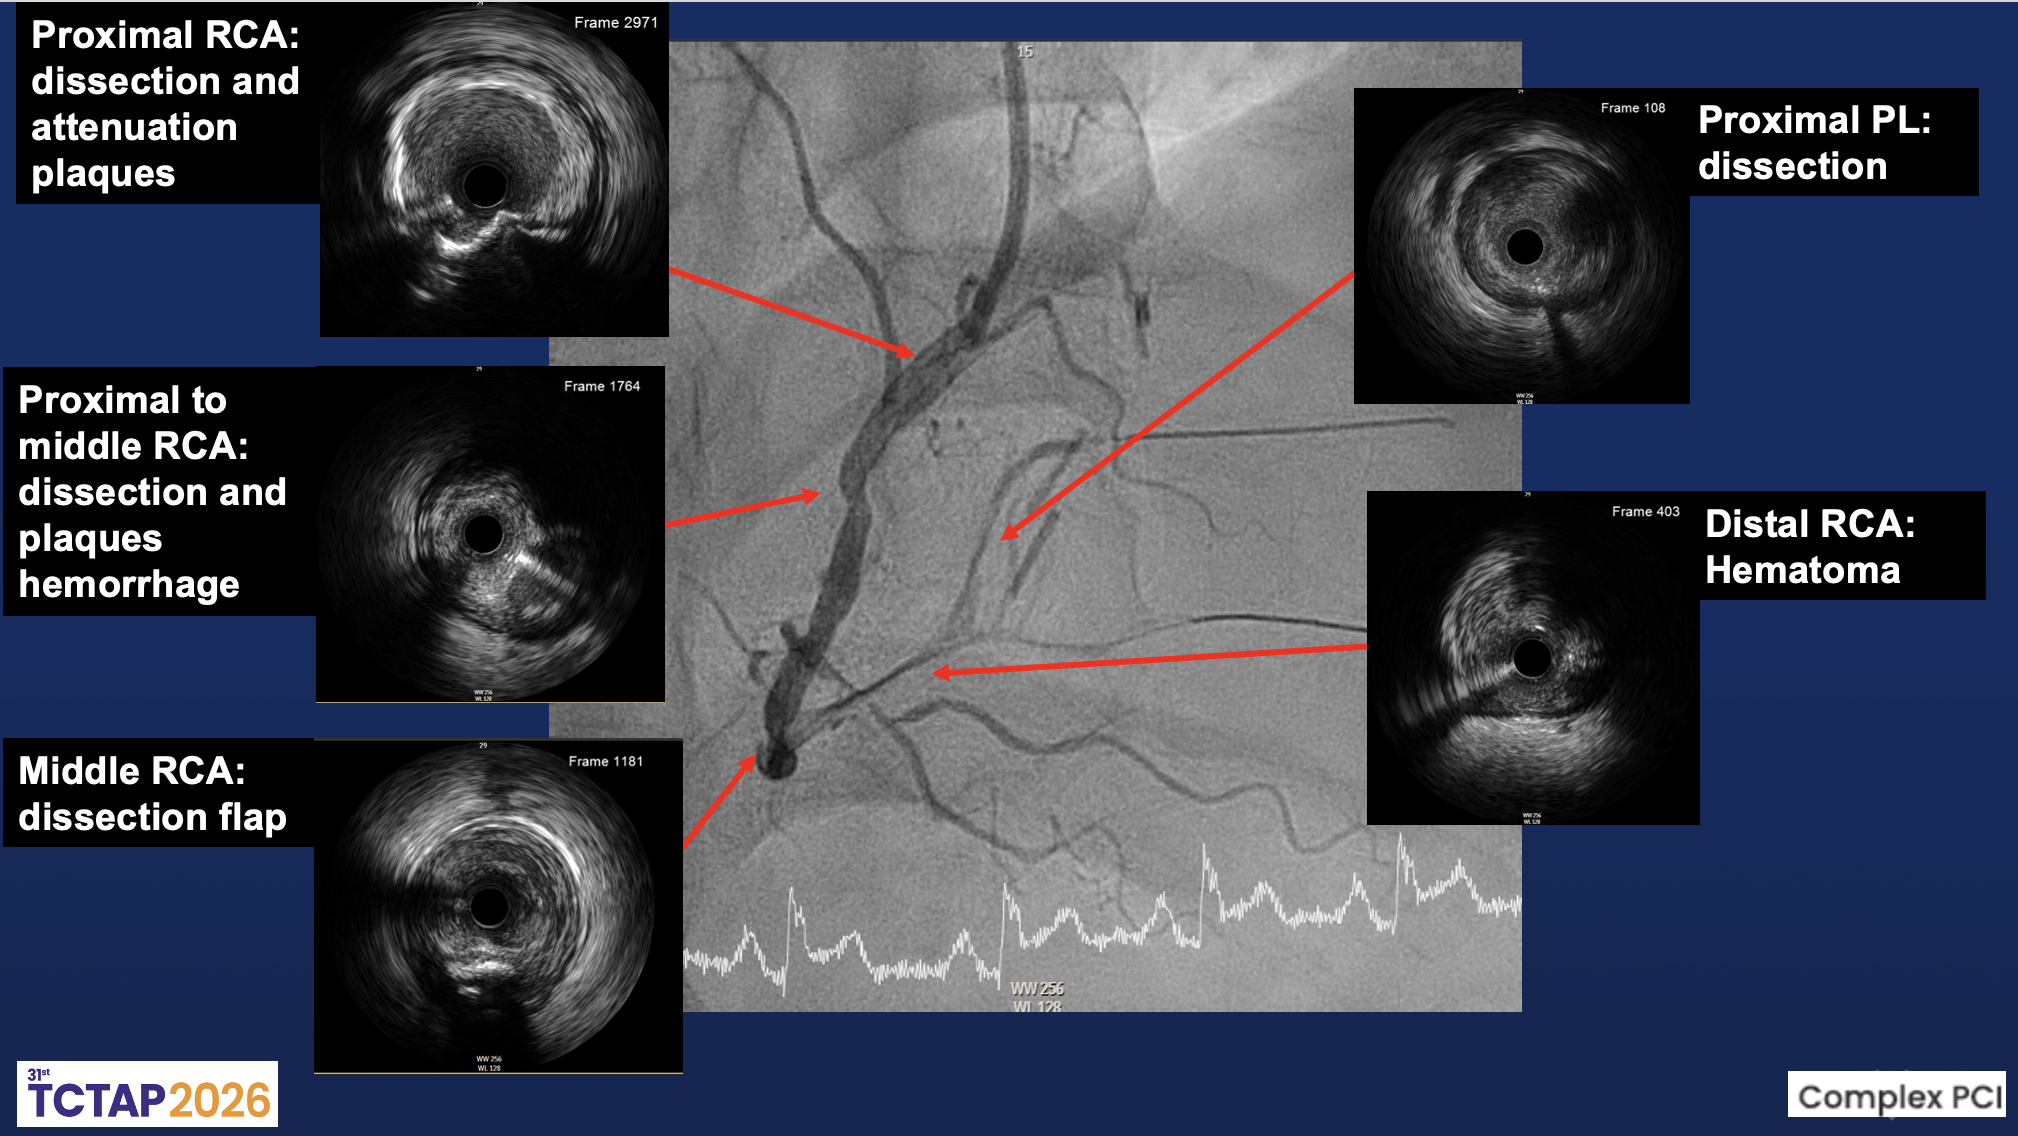

The left main was patent. The LAD showed diffuse eccentric 70–90% stenosis from proximal to distal segments with preserved TIMI 3 flow. The LCx had distal 80–90% and OM2 ostial-proximal 70–80% stenoses with small caliber, giving collaterals to PL. The RCA was dominant with mid 70–80% stenosis and distal diffuse 95–99% stenosis, suggesting a dissection flap with TIMI II distal flow; the PL branch was totally occluded.

Coronary intervention was performed via the right distal radial approach using a 6F SAL 1.0 guiding catheter. The RCA was identified as the culprit vessel. A Sion Black wire successfully crossed the distal RCA lesion into the posterolateral (PL) branch, followed by predilation with a 2.0¡¿20 mm Ryurei balloon. IVUS imaging revealed multiple intramural abnormalities, including diffuse dissection planes, intramural hematoma, and plaque hemorrhage extending from the proximal to distal RCA. The minimal lumen area (MLA) measured 2.26 mm©÷ at the distal RCA and 3.59 mm©÷ at the PL branch, confirming severe luminal compromise with large plaque burden.Further dilation with a 2.5¡¿15 mm Accuforce balloon induced a type B dissection from distal to mid RCA. Sequential stent implantation was performed with a 2.5¡¿38 mm Onyx stent from PL to distal RCA, a 3.0¡¿48 mm Synergy stent in distal RCA, and a 3.5¡¿48 mm X-X stent from mid to distal RCA. Post-dilatation using 3.0¡¿20 mm and 4.0¡¿15 mm Accuforce balloons optimized stent expansion. Repeat IVUS demonstrated good apposition with resolution of intramural hematoma and a minimal stent area (MSA) of 4.61 mm©÷. Final angiography showed restoration of TIMI 3 flow in the RCA and TIMI I–II flow in the PDA without residual dissection.

This case highlights the complexity of PCI in spontaneous coronary dissection. Technical challenges include wiring the true lumen, managing propagation of intramural hematoma, and maintaining side branch patency. IVUS imaging was crucial in identifying multiple dissection planes, hematoma extension, and plaque hemorrhage, guiding appropriate stent sizing and landing zones. Careful wire selection and controlled manipulation are essential to avoid false-lumen entry and further vessel injury. While drug-coated balloon therapy has been reported in selected cases, evidence remains limited.